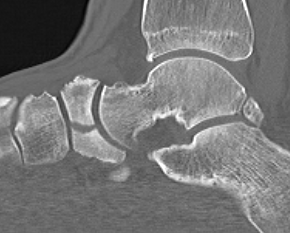

Imaging

Acute displaced navicular fracture